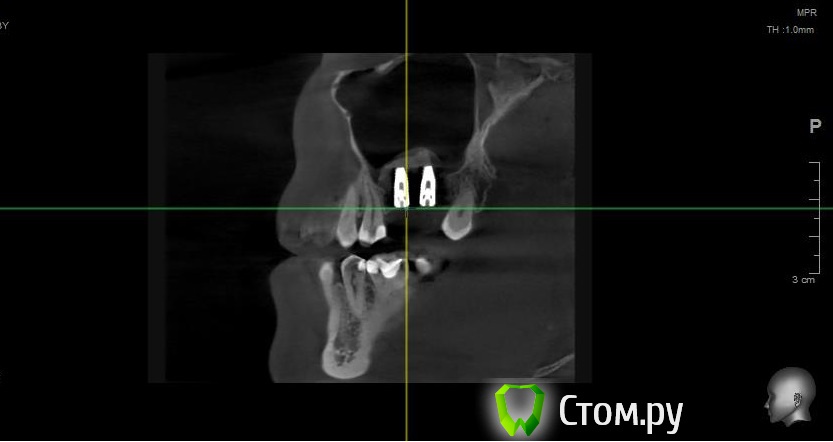

Майло Опубликовано 17 февраля, 2014 Автор Поделиться Опубликовано 17 февраля, 2014 (изменено) Попыталась загрузить снимок кт который был сделан до операции и еще один на всякий случай отснятый на телефон. Изменено 17 февраля, 2014 пользователем Майло Ссылка на комментарий

Майло Опубликовано 18 марта, 2014 Автор Поделиться Опубликовано 18 марта, 2014 (изменено) Здравствуйте, наконец сделала кт. Сегодня появилась небольшая боль над правой бровью (после лазера прошла, к вечеру появилась опять). Насморк и заложенность присутствуют. Еще сегодня опять поговорила со своим хирургом имплантологом. По симптомам сказал, что похоже присоединилась какая-то лор болячка и наверное надо сходить к лору. По кт сказал, что все нормально. Немного сужена пазуха справа, но учитывая, что я аллергичная, это нормально. Про капли типа Полидекса, сказал спросить у лора. Завтра я делаю последний лазер, по прежнему промываю нос Отривином Бэби (мне так удобней), пью кларитин, "выбиваю" нос по необходимости, но стараюсь пореже (2-3 раза в день). Еще он отдал кт через 2 недели после имплантации, на всякий случай прикреплю и этот снимок. Самый первый снимок кт был сделан через 2 недели после имплантации. Второй и третий сегодня. Подскажите, я так понимаю данное кт не показывает есть ли у меня гайморит? (к лору смогла записаться аж на 26-е) И все равно хотелось бы узнать ваше мнение по поводу состояния имплантов, есть ли там воспаление или "нагноение"? Изменено 18 марта, 2014 пользователем Майло Ссылка на комментарий

Майло Опубликовано 18 марта, 2014 Автор Поделиться Опубликовано 18 марта, 2014 (изменено) Решила еще добавить пару кадров своих пазух, вначале показалось что справа что-то есть (рис1), потом поняла это костный материал и импланты (рис2). Надеюсь так должно быть. И еще вопрос, может и "тупой", такое яркое свечение имплантов, особенно заметно на фото в профиль, это нормально? Изменено 18 марта, 2014 пользователем Майло Ссылка на комментарий